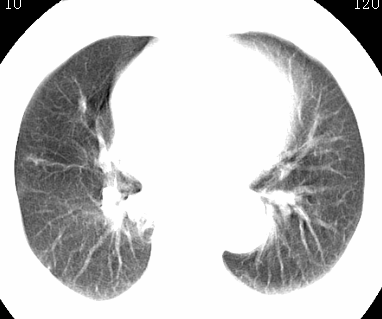

标题: CT26680:肺部右下肺静脉干结节的界定 [打印本页]

标题: CT26680:肺部右下肺静脉干结节的界定

经追查说有支扩咯血病史,但不确定

考虑1、周围型肺癌,2肺静脉畸形,前者可能大,建议增强检查。

考虑1、周围型肺癌,2肺静脉畸形,前者可能大,建议增强检查。支持!

不排除右肺下叶周围型肺癌可能。